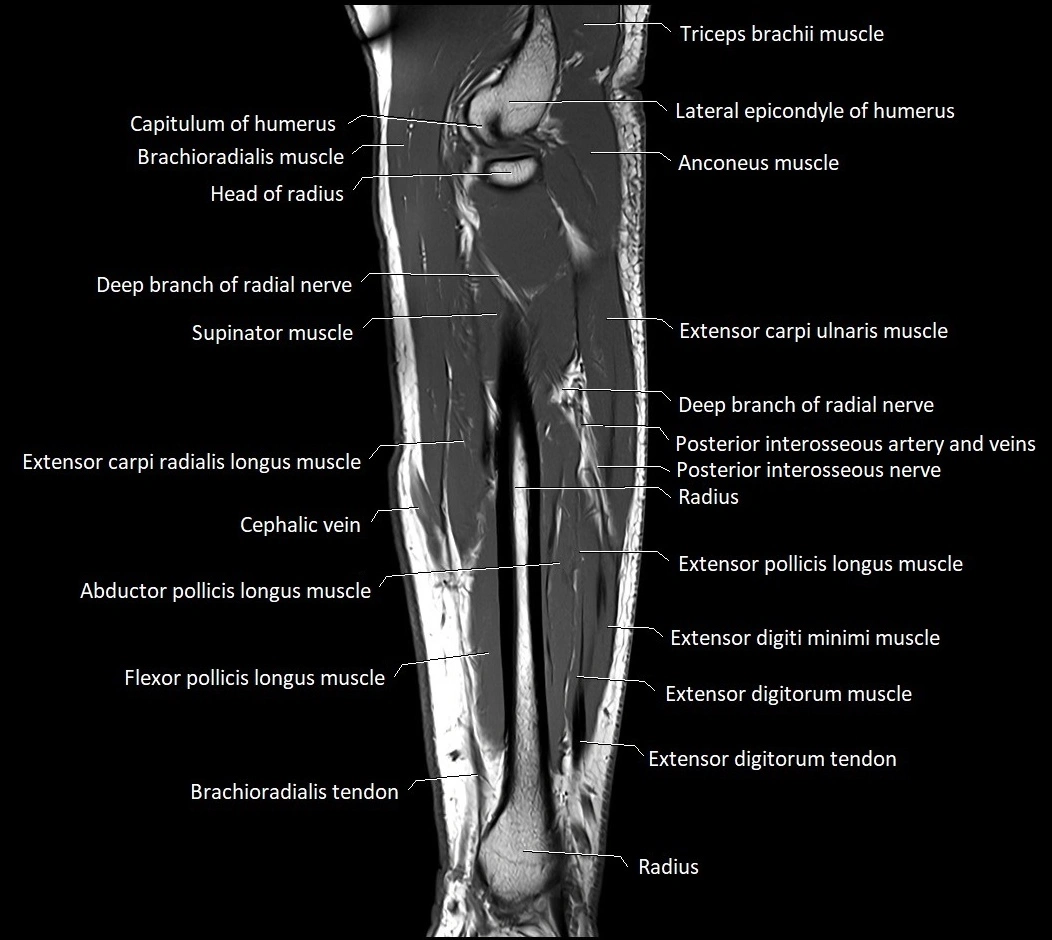

MRI images

image